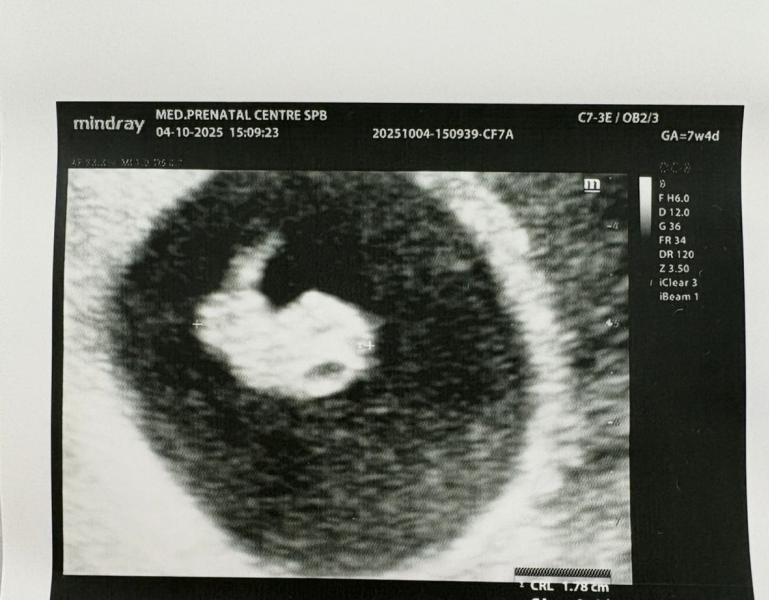

Креветка моя❤️ Уже сердечко стучит 176 ударов, а ктр уже 18мм, опережает на 1.5 недели срок по месячным(привет ранняя овуляция). По месячным 7.4, а по узи 9 недель почти) Вот только вчера же тряслась над тестом, сердце заходилось, а сегодня уже мне показывали зачатки ручек и ножек🙏🏻

расти, крошка🙏🏻